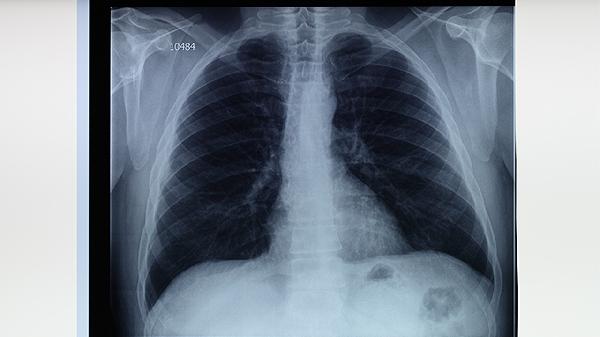

肺结核患者对抗结核药物过敏时,应保持充足营养,适当进食高蛋白食物如鸡蛋、瘦肉,补充维生素丰富的新鲜蔬菜水果。注意休息避免劳累,居住环境保持通风良好。严格戒烟戒酒,减少呼吸道刺激。遵照医嘱定期复查胸部影像学和痰菌检查,不可自行停药或更改方案。出现皮疹、发热等过敏症状需立即就医,外出时佩戴口罩防止传播。患者家属建议进行结核筛查,婴幼儿应及时接种卡介苗。